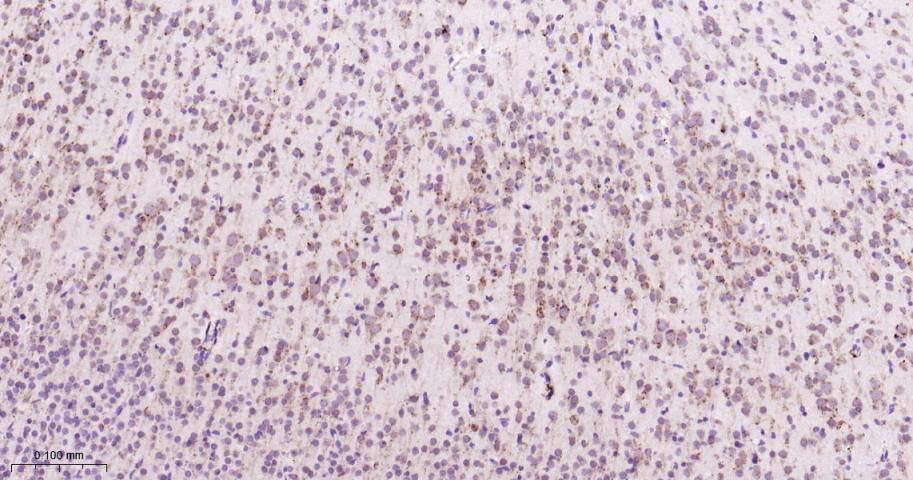

Paraformaldehyde-fixed, paraffin embedded Rat Cerebrum; Antigen retrieval by boiling in sodium citrate buffer (pH6.0) for 15 min; Antibody incubation with GRP94 Monoclonal Antibody, Unconjugated(bsm-61455R) at 1:200 overnight at 4°C, followed by conjugation to the bs-0295G-HRP and DAB (C-0010) staining.